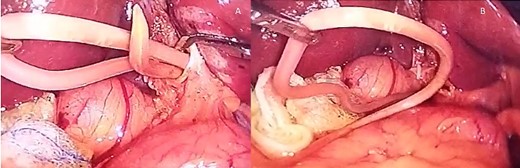

(A) The Ascaris is seen inside the bile duct; (B) the Ascaris is completely removed from the bile duct, choledochotomy is seen as well.

At laparoscopy, multiple adhesions from the omentum to the gallbladder were found. The adhesions were released, and after the bile duct was exposed, a 1.5 cm choledochotomy was done.

Purulent bile was drained, and a 12 × 1.5 cm A. lumbricoides was found in the bile duct, causing complete obstruction. The roundworm was removed, and a cholangiogram was done afterward, ensuring that the bile duct was clear (Fig. 2a and b).